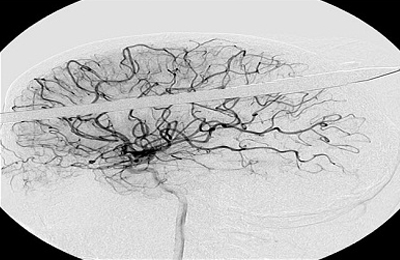

Η βέργα «χτύπησε» το Yasser μερικά εκατοστά πάνω από το δεξί του μάτι, καρφώθηκε στο κρανίο του και ακινητοποιήθηκε στο δεξί λοβό του εγκεφάλου του.

«Είναι θαύμα που δεν χτυπήθηκε κανένα από τα βασικά αιμοφόρα αγγεία του εγκεφάλου…» δήλωσε ο νευροχειρουργός Ross Bullock. «το πιο δύσκολο είναι να αντισταθείς στον πειρασμό να τραβήξεις αυτό το πράγμα έξω».

Οι γιατροί σταθεροποίησαν τη βέργα και απομάκρυναν κομμάτι μήκους 47 εκατοστών, πριν βγάλουν τις ακτινογραφίες. Στη συνέχεια χρειάστηκαν τρεις ώρες για να απομακρύνουν τη λόγχη από τον Υasser, ο οποίος νοσηλεύεται σε σοβαρή, αλλά σταθερή κατάσταση.